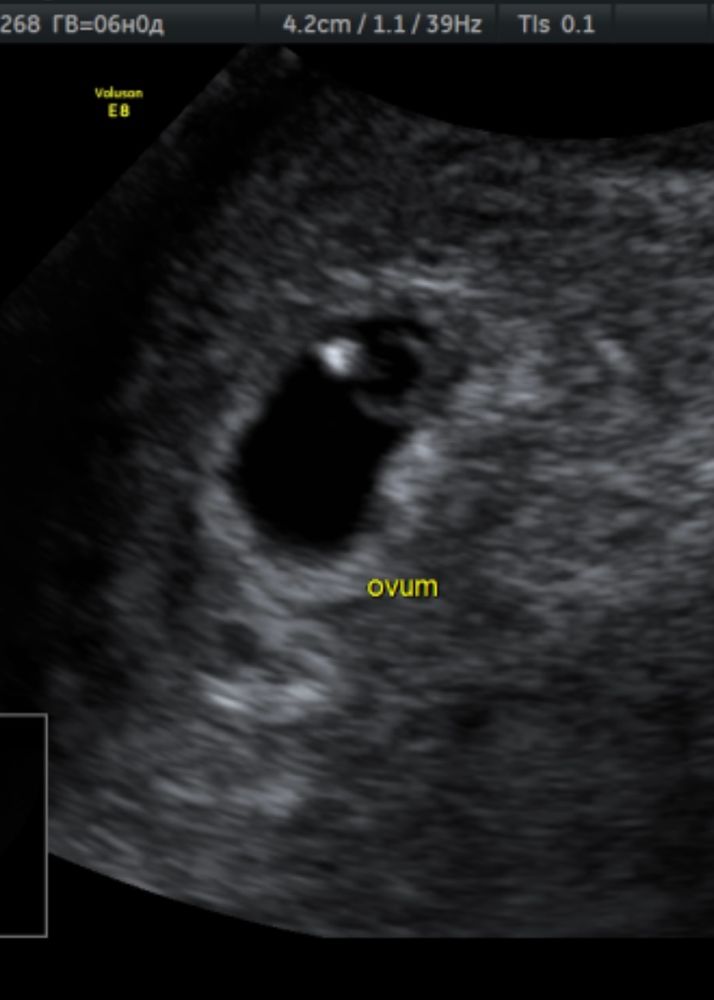

Изображение Это 6 недель и 4 дня, эмбрион bravo gun, вот моё УЗИ 4 недели и 6 дней, пя 7 мм про желточный не слова,но его видно на УЗИ, фото кстати тоже фиговое Изображение